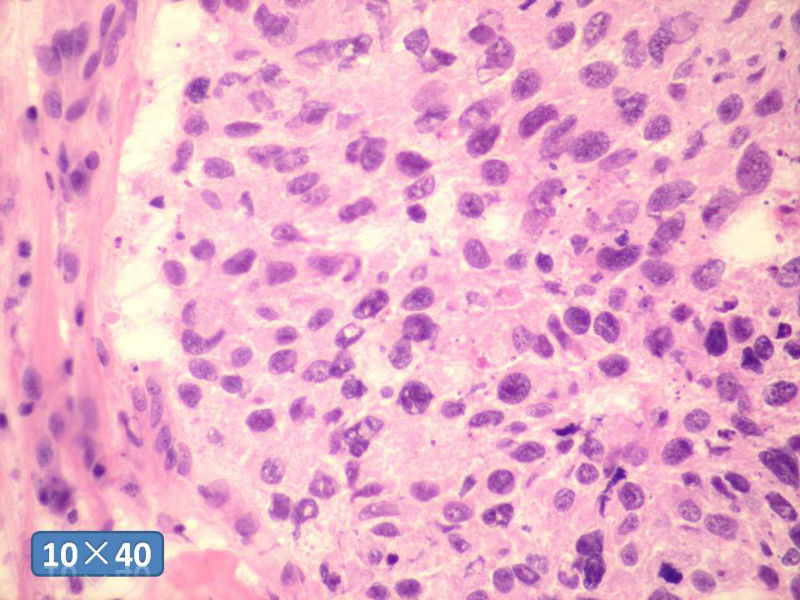

女性,50岁,乳腺肿物,冰冻切片(图1-25)

HE

可惜染色苏木素太浅,实在不敢发言

IDC